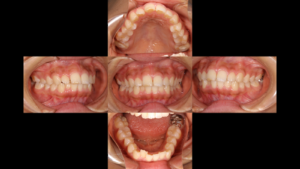

みなさん、こんにちは。 鎌倉ルクス歯科・矯正歯科の院長の岡です。今回もワイヤー矯正のお話です。

以前のブログで「6番(第一大臼歯)を抜歯して出っ歯を改善した症例」をご紹介しましたが、今回もそれと通ずる「抜歯の選択肢」にこだわったケースです。

今回の課題:出っ歯と「寿命の短い奥歯」

今回の患者様は、上下ともに小臼歯の抜歯を行っていますが、ポイントは上顎の奥歯(7番)の扱いです。

課題1: 重度の出っ歯(上顎前突)

課題2: 7番(第二大臼歯)が失活歯(神経がない歯)で、将来的な破折や再感染のリスクが高い

課題3: ガミースマイル(笑うと歯茎が目立つ